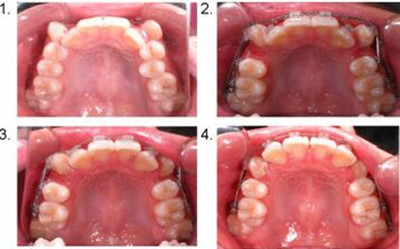

想要具体了解牙齿不齐的危害 点击【在线咨询】直接问医生!方便!快捷牙齿不齐又称错颌畸形,是指在生长发育过程中,由先天的遗传因素或后天的环境因素,如疾病、口腔不良习惯、替牙异常等导致的牙齿、颌骨、颅面的畸形,主要有:牙齿排列不齐、上下牙弓间的颌关系异常、颌骨大小形态位置异常等。牙齿不齐是怎样造成的?错颌畸形形成因素及其机理是错综复杂的。直接与医院在线医师一对一通话,方便!快捷!了解详情就医指导。

第一、严重影响牙周组织健康及口腔卫生。牙列不齐,特别是牙齿拥挤,一方面使口腔菌斑易于附着,另一方面因牙刷难于接触而不易清洁,因而牙周组织,如牙龈、牙槽骨较易产生炎症,出现牙龈肿胀、出血、口腔异味等症状,久而久之如果严重累及牙槽骨,则可出现牙齿松动,从而造成严重后果。